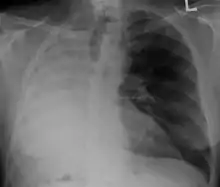

A pneumonectomy (or pneumectomy) is a surgical procedure to remove a lung. Removal of just one lobe of the lung is specifically referred to as a lobectomy, and that of a segment of the lung as a wedge resection (or segmentectomy).

The most common reason for a pneumonectomy is to remove tumourous tissue arising from lung cancer. In the days prior to the use of antibiotics in tuberculosis treatment, tuberculosis was sometimes treated surgically by pneumonectomy.

The operation will reduce the respiratory capacity of the patient; before conducting a pneumonectomy, the surgeon will evaluate the ability of the patient to function after the lung tissue is removed. After the operation, patients are often given an incentive spirometer to help exercise their remaining lung and to improve breathing function. A rib or two is sometimes removed to allow the surgeon better access to the lung.